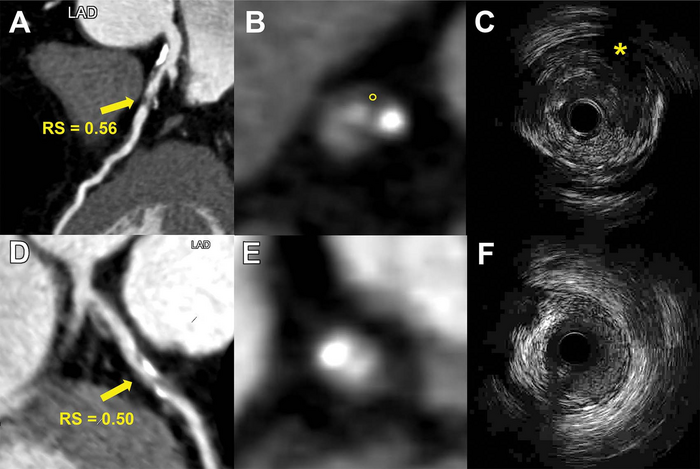

OAK BROOK, Ill. – Researchers are using an approach called radiomics to predict future cardiac events like heart attacks, according to a study published in Radiology , a journal of the Radiological Society of North America ( RSNA ). Radiomics allows researchers to extract quantitative, or measurable, data from CT images that can reveal disease characteristics not visible in the images alone.

Researchers in China developed a radiomics model that uses information from coronary CT angiography images to assess plaque vulnerability. They developed the model in 299 patients. They then studied the approach in 708 patients with suspected coronary artery disease.

The model enabled the detection of vulnerable plaques associated with an increased risk for major adverse cardiac events like heart attacks. A high radiomic signature was independently associated with these events over a median three-year follow-up.

“The results of this study are encouraging and exciting,” said study co-lead author Long Jiang Zhang, M.D., Ph.D., from the Department of Radiology at Jinling Hospital, Medical School of Nanjing University in Nanjing, China. “Radiomics provided a more accurate approach to detect vulnerable plaques compared to conventional coronary CT angiography anatomical parameters.”